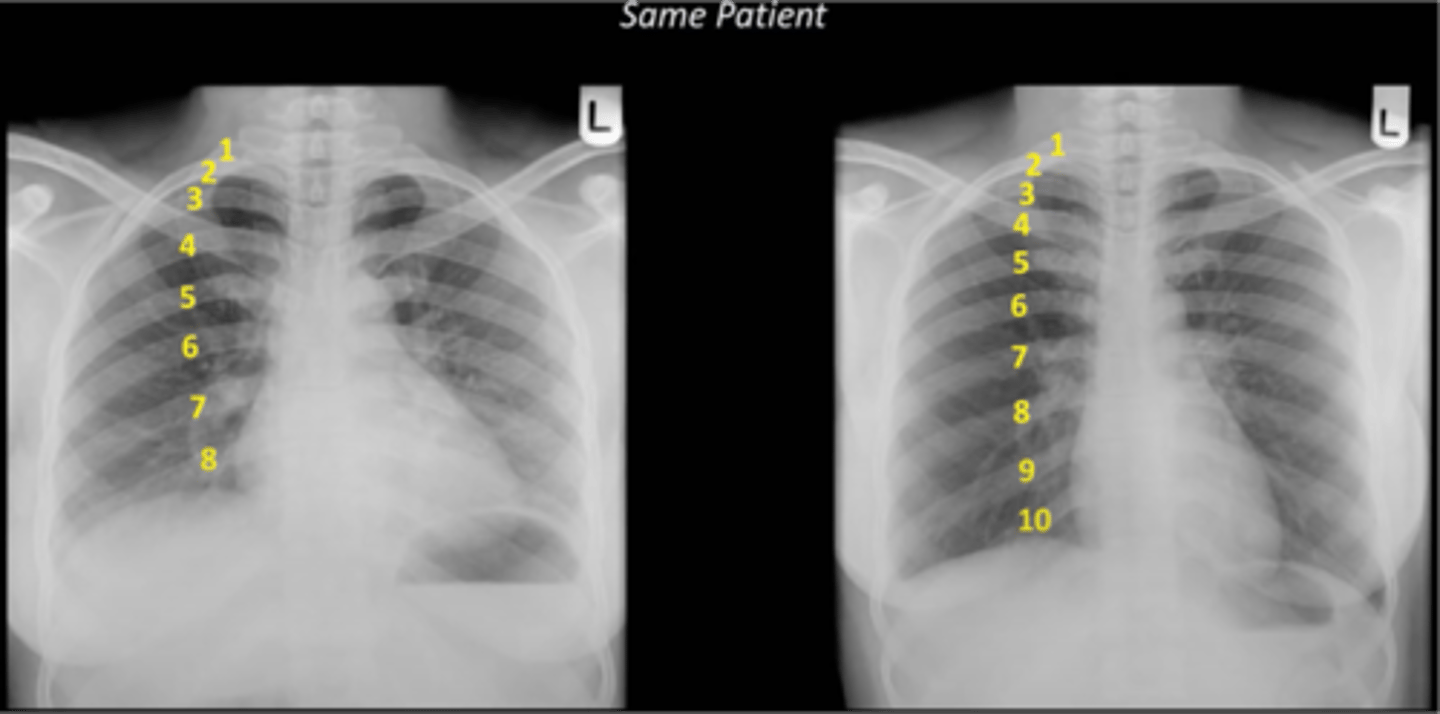

-inspiration: we need good inspiratory effort

-should see 9-10 posterior ribs or 6-7 anterior ribs (7th piercing the diaphragm)

What does the I stand for in RIPE

consequences of inadequate inspiration